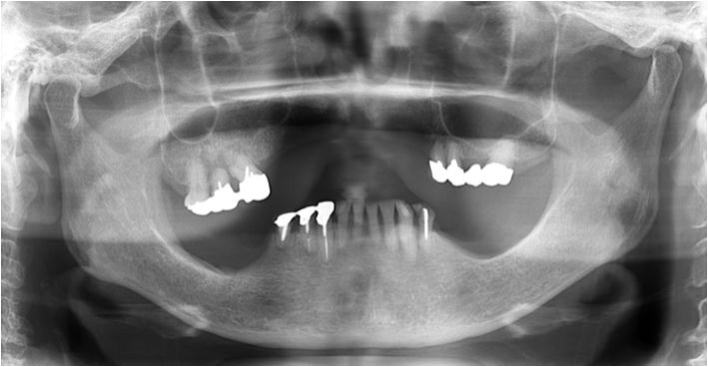

上の2枚のレントゲンは上下奥歯の咬合関係が無く左右前後の咬合崩壊が起きています。

|

この患者様は、〇 の歯以外は全て抜歯せざるを得ない状態でした。

歯がない箇所の放置は、咬合崩壊を必ず起こします。